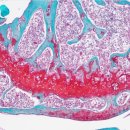

Servicebio Safranin O-Fast Green Staining Reagent (G1053)는 연골을 선명한 빨강색으로, 골형성 부위를... 제품명: Safranin O-Fast Green Staining Reagent For Bone Tissue 제품번호: G1053-100ML 용량: 2×100 mL (Safranin O + Fast...